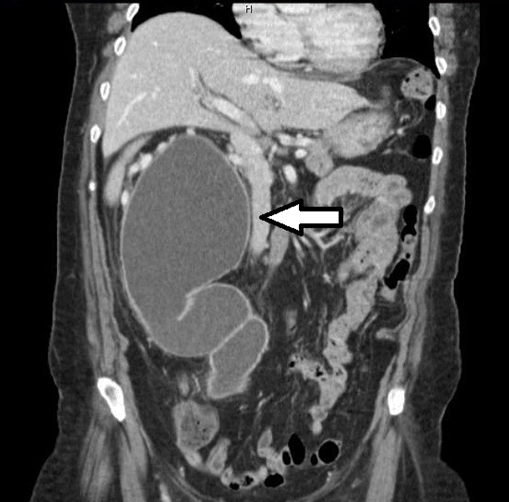

A 70-year-old female presented with right back pain and fever. Six months earlier was submitted to hysterectomy and bilateral salpingo-oophorectomy for an ovarian epithelial cancer (stage IA). On physical examination, she had chills, fever, and tenderness at the right costovertebral angle. Blood tests indicated acute renal failure and marked elevation of C-reactive protein. In renal ultrasound, a mild right hydronephrosis was identified, and the respective ureter proved to be impossible to visualize due to the presence of a large cystic-like structure (19 cm of longitudinal size). As there was a suspicion of obstructive pyelonephritis, a renal scintigraphy was performed indicating the presence of a significant unilateral obstruction. Non-contrast computed tomography (CT) scan showed a markedly distended right ureter (up to 9.5 cm in diameter) with tortuosity (Figure 1) and (Figure 2) (Figure 2), not evident in previous follow-up CT scan. No calculus or other anatomical urologic abnormalities were found. The patient underwent percutaneous nephrostomy, which drained 1500 cc of purulent fluid. Escherichia coli were isolated and adequate antibiotic therapy was instituted. The clinical condition of the patient declined progressively and had passed away after three days.

Figure 2: Coronal cuts on CT scan showing an impressive image of a massively dilated and tortuous right ureter.